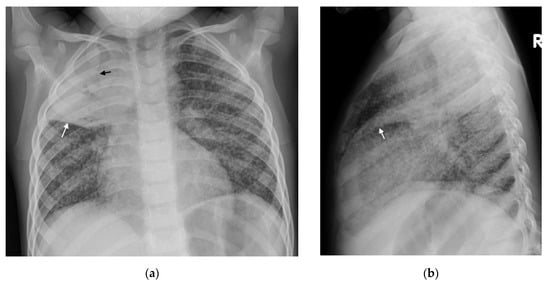

Figure 1. (a,b): Right Paratracheal and Hilar lymphadenopathy before and after treatment. (a) AP chest radiograph of a child at presentation, who later was later confirmed to have pulmonary TB, demonstrates a right-sided lobulated cardio-mediastinal margin with filling of the right hilar point (white arrows) and consistent with right paratracheal and hilar lymphadenopathy. The trachea is displaced to the left, slightly bowed and shows decreased calibre just superior to the carina. There is an oval density seen separately from the scapula in the right lung apex, which in conjunction with the lymphadenopathy, constitutes the Ghon Complex. (b) Post-treatment AP chest radiograph demonstrates complete resolution of the parenchymal focus and lymphadenopathy with a normal right cardio-mediastinal border and return of the trachea to its normal shape and position.

Right hilar adenopathy (a lobulated hilar opacity on chest radiograph) obscuring the hilar point, Figure 1, is more commonly observed than left, with left hilar nodes only evident when extending beyond the left cardiac border [27]. Paratracheal adenopathy may be difficult to distinguish from other mediastinal tissues, such as the thymus, but will extend beyond the normal mediastinal contours, and may result in airway compression and deviation [27]. Left paratracheal lymphadenopathy is rarely observed in isolation, most commonly co-existing alongside other regions of mediastinal lymphadenopathy [27]. Sub- or retro-carinal lymphadenopathy is typically seen on the lateral projection as lobulated densities inferior and posterior to the bronchus intermedius, which, in combination with the more superior aortic arch and pulmonary arteries result in the well described “doughnut sign” (Figure 2).